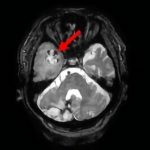

断層撮影

手術前1

手術前2